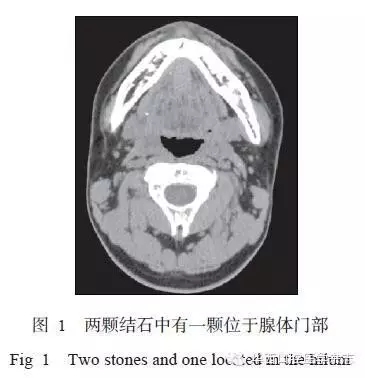

所有患者術(shù)前均行下頜骨CT[7]及唾液腺功能顯像檢查,結(jié)石位置要求位于下頜牙列雙側(cè)最后點(diǎn)連線后方,或位于下頜下腺腺體內(nèi)。若為多顆結(jié)石,至少有一顆符合此標(biāo)準(zhǔn)(圖1)。術(shù)前唾液腺功能檢查提示患側(cè)攝锝功能基本正常,排泌功能明顯下降。排除標(biāo)準(zhǔn):患側(cè)唾液腺無(wú)攝锝功能。